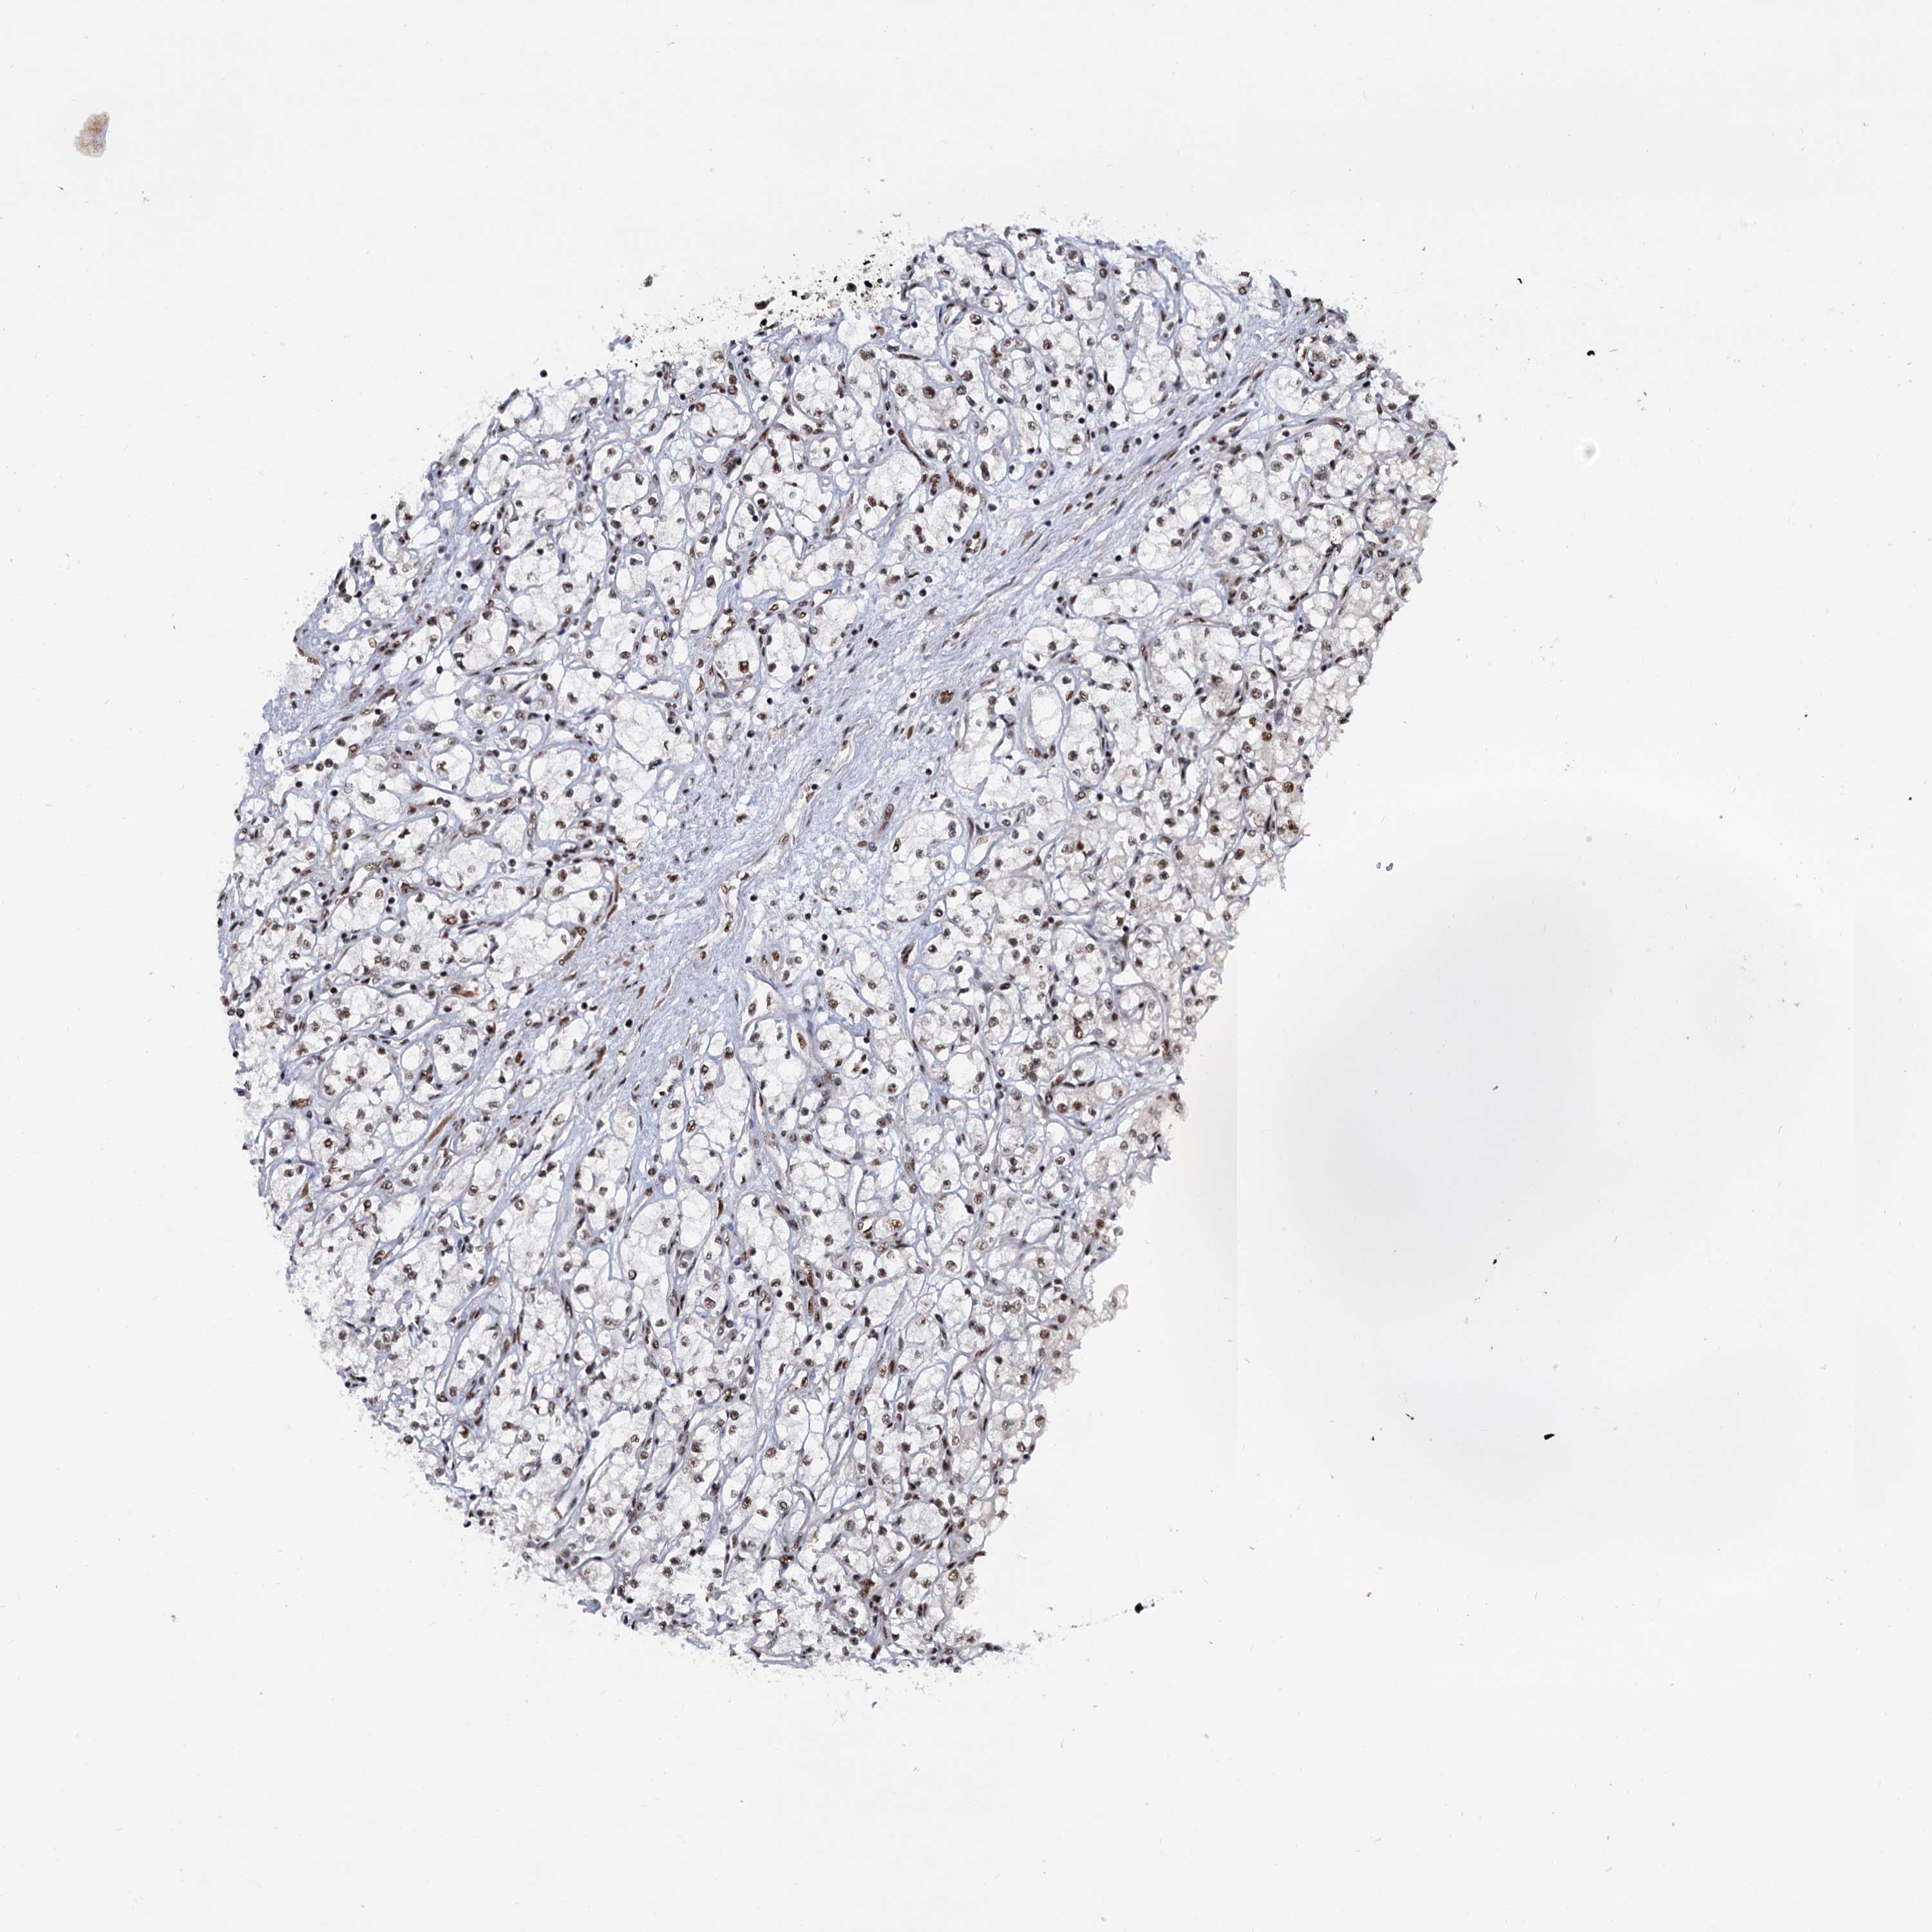

Renal cancer

Kidney renal papillary cell carcinoma

WBP4 is not prognostic in Kidney Renal Papillary Cell Carcinoma (TCGA)

Best expression cut offi